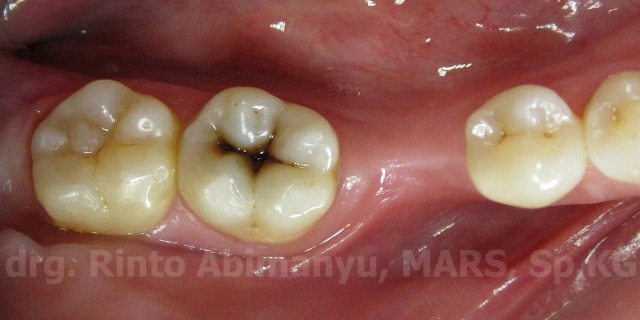

Pasien awalnya datang ingin membersihkan karang gigi, dan tidak ada keluhan lain pada giginya… Setelah saya cek ternyata terdapat karies di gigi 47 nya, kemudian saya tampilkan di layar tv agar pasien bisa melihat keadaan giginya… Nah bener saja, pasien kaget melihat giginya ada yang bolong, karena selama ini tidak ada rasa ngilu…

Begini keadaan giginya..

Setelah dijelaskan bahwa walaupun dari luar terlihat tidak luas lubangnya tetapi bisa saja di dalamnya berbeda… Pasien setuju untuk dilakukan penambalan…